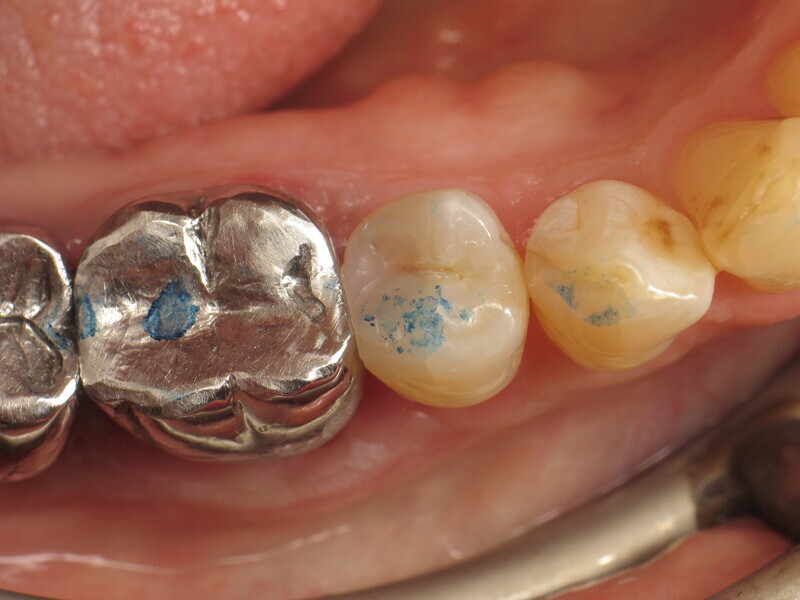

Enfin, une photopolymérisation est réalisée pendant 20 secondes (puissance ≥ 1 000 mW/cm2 ; Fig. 14). Le maquillage est ensuite réalisé avec un composite teinté photopolymérisable (FinalTouch, VOCO, couleur orange, Fig. 15). Après 20 secondes de durcissement du composite de maquillage (Fig. 16), un gel de glycérine est appliqué (Fig. 17) puis la photopolymérisation finale est effectuée (Fig. 18). L’excédent est ensuite retiré et la surface est polie (Fig. 19). Pour ajuster l’occlusion, du papier à articuler est utilisé pour visualiser les points de contact (Fig. 20) et apporter les corrections nécessaires (Fig. 21). Le résultat final est très naturel (Fig. 22).

La comparaison des radiographies pré et postopératoires montre la qualité du traitement (Fig. 23). Grâce aux excellentes propriétés d’application du composite thermovisqueux, la restauration ne contient aucune bulle d’air. De plus, il existe une uniformité entre les deux composites utilisés en termes de visibilité aux rayons X et dans l’ensemble, la restauration apparait homogène, sans transitions visibles entre le composite de base flow et le composite de remplissage bulk. La radiographie préopératoire n’a pas permis de montrer toute l’étendue de la lésion. Ce n’est qu’au cours d’un traitement qu’il est devenu évident qu’une préparation très approfondie devait être effectuée afin d’éliminer complètement la structure dentaire affectée. Afin de maintenir la vitalité de la pulpe, une densibilisation a été réalisée avant la restauration composite proprement dite.